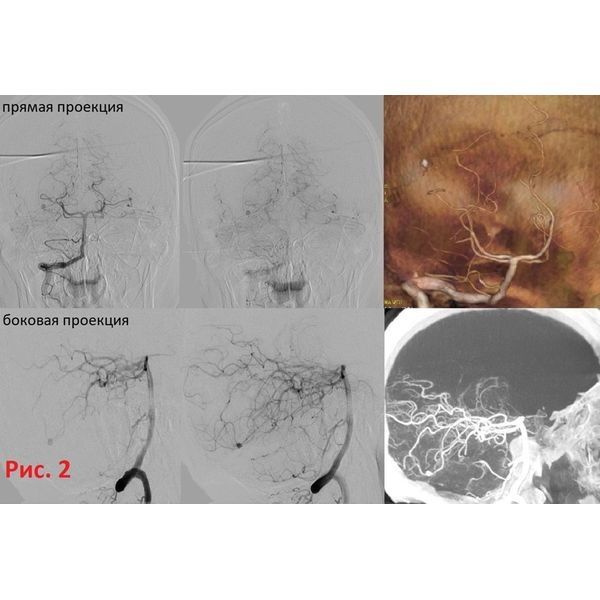

На КТ-ангиографии и прямой церебральной ангиографии выявили источник внутримозгового кровоизлияния — дистальную аневризму (ближе к дальней части сосуда) шпорной ветви правой задней мозговой артерии. Размер образования — до 3 мм.

Под общим наркозом в правую позвоночную артерию ввели катетер. При попытке селективного заведения микрокатетера Excelsior SL-10 (Stryker) при помощи микропроводника PT2 0,014” (Boston Scientific) произошёл разрыв правой задней мозговой артерии на уровне сегмента P3. Вероятно, это было связано с выраженной извитостью P2–3 сегментов и возможным инфекционным артериитом — воспалением, вызывающим изменение стенок артерий. Без промедления выполнили окклюзию (блокировку) задней мозговой артерии на уровне P2 сегмента при помощи микроспиралей Target (Stryker).